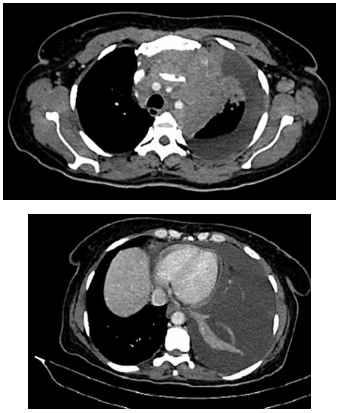

Mulher de 52 anos apresenta quadro de quatro semanas

de dispneia progressiva, dor torácica do lado esquerdo

e tosse seca. O histórico é relevante para histerectomia

para miomas uterinos há três anos. A oximetria de pulso

é de 93% em ar ambiente. Exames séricos: hemoglobina: 9,8 g/dL; d-dímero: 770 ng/mL. O ultrassom mostra

derrame pleural esquerdo, e a toracocentese revela:

líquido amarelado e levemente turvo; proteína: 6,1 g/dL;

lactato desidrogenase: 5.910 UI/L; pH: 7,44; adenosina deaminase: 12,1 UI/L; contagem de leucócitos:

157.109 células/mm3

(78% linfócitos); coloração de Gram

e cultura para bactérias e fungos permanecem negativos;

a citologia mostra linfócitos abundantes sem células malignas. Imagens da tomografia realizada são mostradas

a seguir: